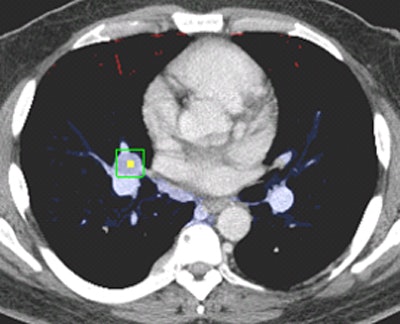

Multiorgan segmentation

The fully automated software identifies eight organs using multiatlas label fusion and the relative position of the node to these organs to assign the IASLC station location.

First is spine segmentation performed using a watershed algorithm that identifies the spine in yellow (the organs are all color-coded). Next comes tracheal and lung segmentations, which use thresholding and morphological operations. Finally, come the other organs, including the esophagus and aortic arch, pulmonary trunk, ascending and descending aortas, superior vena cava, azygous arch, and the heart using the multiatlas technique with joint label fusion, Summers said.

These atlases are then registered to the target image segment and merged via joint label fusion to generate the final segmentation, Summers said.